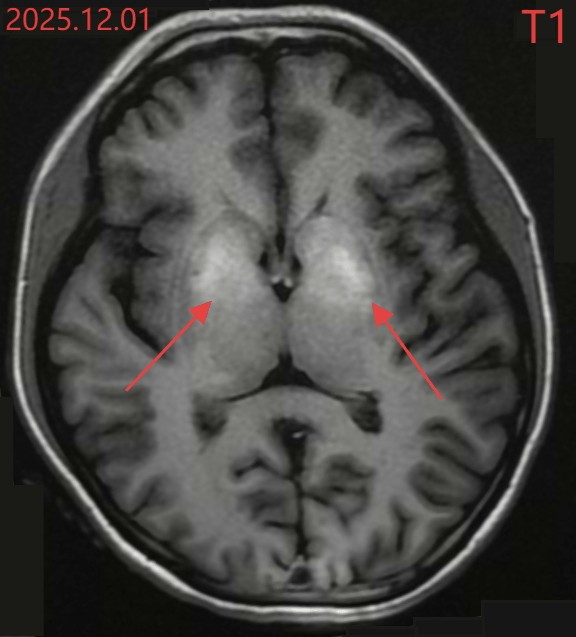

Kết quả chụp cộng hưởng từ sọ não của Tiểu Văn

Các xét nghiệm chuyên sâu sau đó còn đáng lo ngại hơn. Chỉ số HbA1c (đường huyết trung bình trong 2–3 tháng) của Tiểu Văn đạt 17,7%, trong khi mức bình thường cần dưới 6,5%. Điều này cho thấy tình trạng tăng đường huyết đã tồn tại kéo dài trong thời gian dài mà không được phát hiện. Chụp cộng hưởng từ (MRI) não cho thấy vùng hạch nền, khu vực nằm sâu trong não, chịu trách nhiệm điều phối vận động, đã xuất hiện tín hiệu bất thường. Các bác sĩ ví đây như “vết bỏng” của não do đường huyết cao kéo dài gây ra.